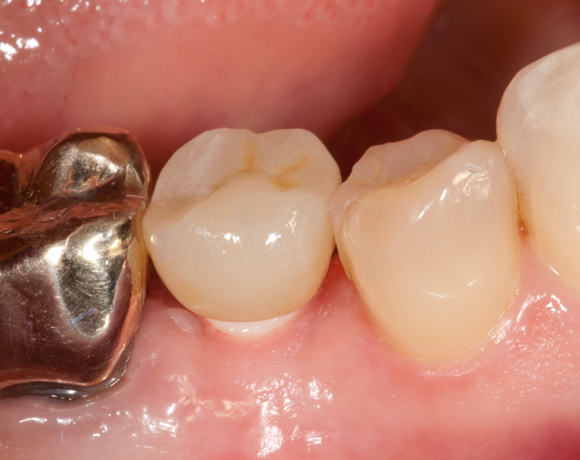

Bei diesem Patientenfall wird die offene Abdrucknahme gezeigt und die Herstellung einer Krone auf einen CAD/CAM Pfosten.